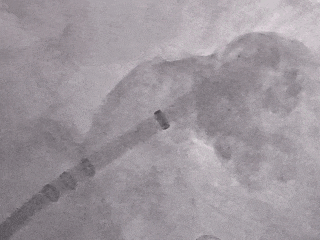

术中DSA肝位造影:大鸡翅型左心耳

心耳上缘内壁凹陷

肝位左心耳测量

开口24.97mm

深度25.25mm